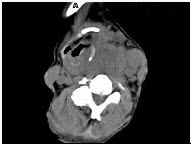

上图处理前: